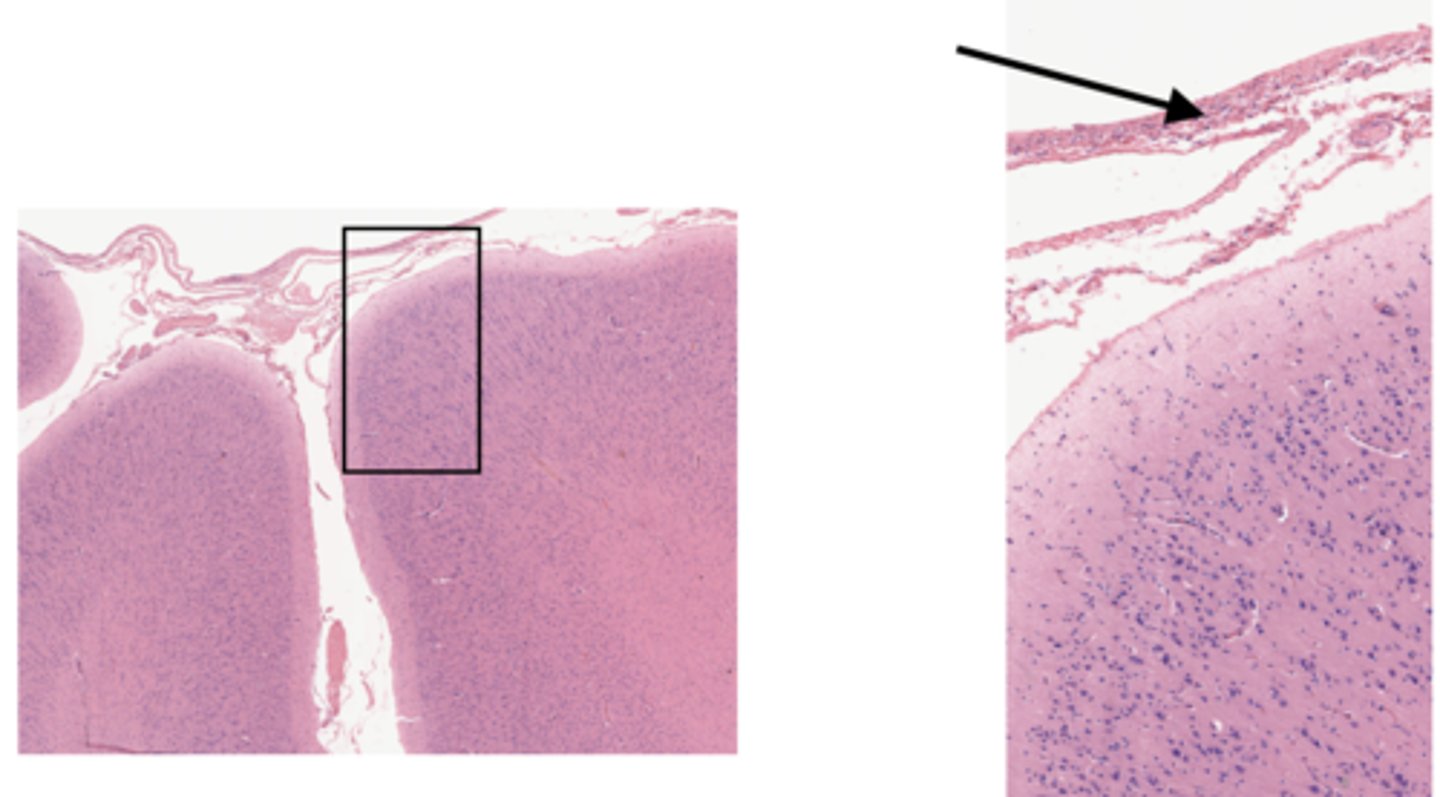

Identify the specific part of the brain

cerebrum

Identify the layer of the cerebrum

molecular layer

pia mater

arachnoid

pyramidal layer

white matter